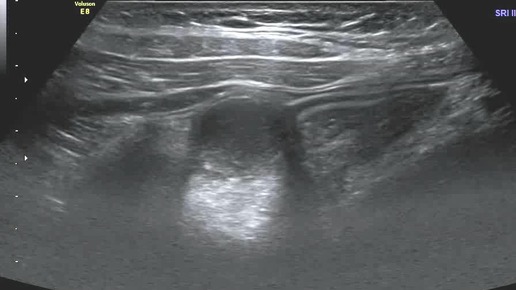

Ультразвуковые находки от врача УЗД Зорина Я.П.